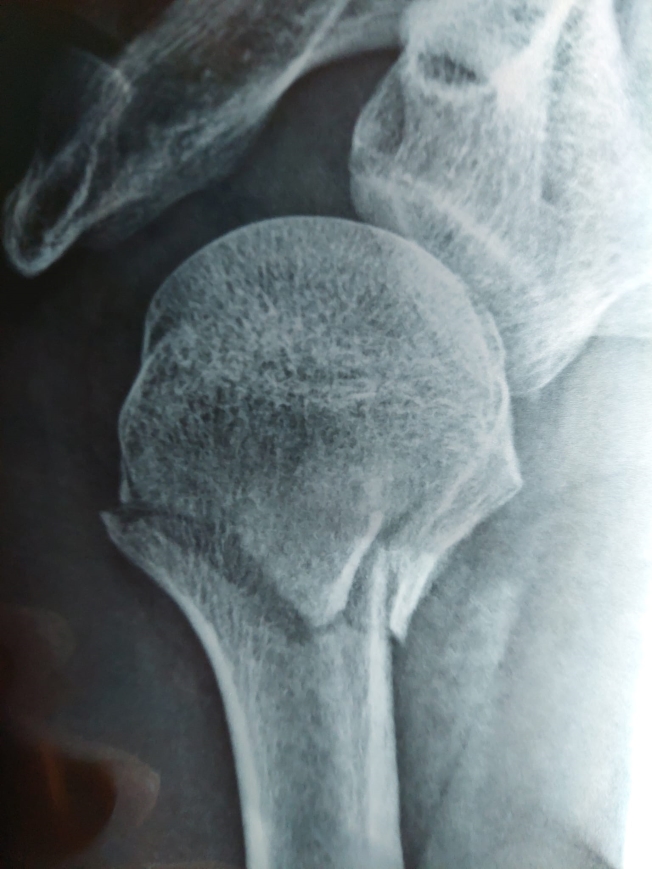

關節脫骹骨折復位

治療前 (2025年12月7日)

治療後 (2026年1月21日)